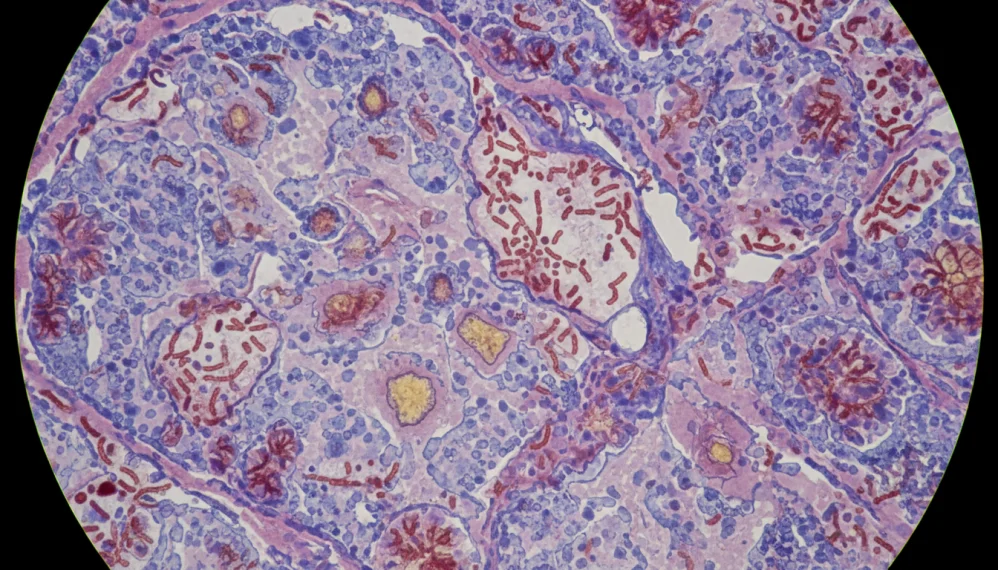

Nocardia este o bacterie capabila sa produca in parenchimul pulmonar necroza supurativa si abcese. Manifestarile propriu zise ale bolii depind insa de locul inocularii, de tropismul bacteriei pentru tesutul respectiv, de capacitatea acesteia de a supravietui atacului initial al sistemului imun (in principal al leucocitelor neutrofile), precum si de agresivitatea raspunsului imun al organismului gazda. Protectia impotriva nocardiozei este realizata prin limfocitele T. Ca urmare, afectiunile in care imunitatea mediata de limfocitele T este afectata, se pot complica foarte usor cu nocardioza pulmonara, cutanata sau chiar diseminata.

- Realizarea unor culturi din produse biologice recoltate: sputa, lichid pleural, lichid din abcese drenate. Aceasta este cea mai buna metoda de diagnosticare, deoarece astfel se poate observa direct agentul microbiologic. Deoarece Nocardia este o bacterie ce se dezvolta geu, laboratorul de microbiologie trebuie intotdeauna avertizat cand se doreste cultivarea produsului biologic pe medii speciale pentru Nocardia. Nocardia este izolata in aproximativ 5 zile.